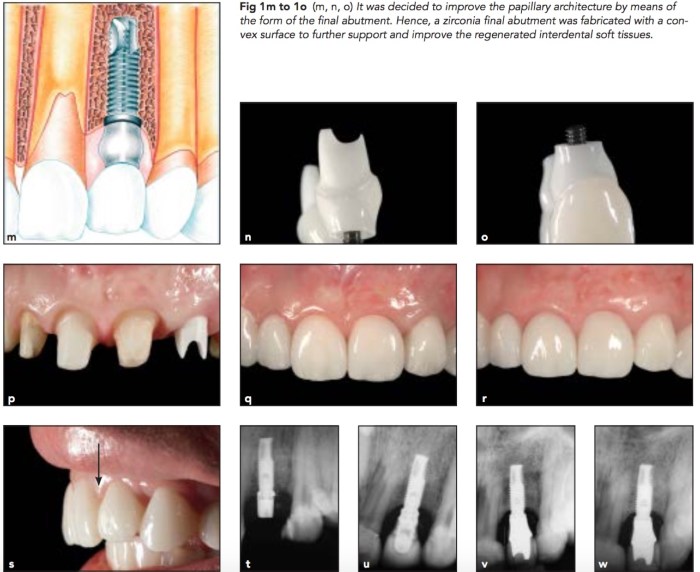

之前的那篇文章是用CT graft去補缺損,但是若是缺損超過3mm, 沒辦法單純補肉怎麼辦?或是隔壁鄰牙牙周狀況太差沒有骨頭可以支撐?還是要補骨補肉雙管齊下,另外配合convex custom abutment。但是長期來說有沒有問題?真的很難說,盡人事聽天命。

手術部分就是盡力去補,作者喜歡自體骨加上Emdogain,也有補CT graft。然後在abutment方面有加上convex以撐起牙肉。文章內容寫得很詳細,Dr. Urban的文章算是不藏細節的了。